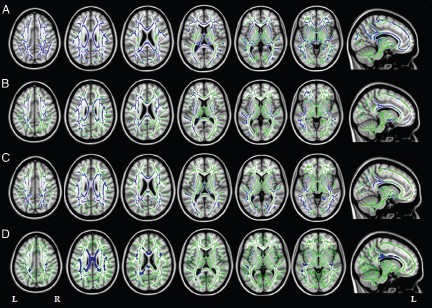

La fundación cien ( centro de estudios de enfermedades neurologicas ) en el año 2012 realizo un estudio piloto en el cual quedo demostrado que la resonancia magnética y la automatización de los procesos de cuantificación y análisis de la inteligencia artificial pueden diferenciar entre un paciente con deterioro cognitivo leve (DCL) o algún tipo de demencia permitiendo así el diagnostico precoz. Evaluaron cuatro grupos de pacientes:

- Pacientes cognitivamente sanos (CS),

- Pacientes con deterioro cognitivo leve (tipo amnesico DCLa y DCLm multidominio)

- Pacientes con EA.

La exactitud en diferenciar entre un CS y una EA fue superior al 95% y en el caso de DCL y EA del 90%. También gracias a este estudio se pudo constatar cuales son las técnicas mas eficientes para detectar diferencias significativas entre los distintos grupos evaluados, la ASL (arterial spin labeling) es muy buena para diferenciar CS de DCLa pero no para DCLm de EA al contrario que la espectroscopia. La técnica que obtuvo mejores resultados fue la volumetría aunque también destacan los investigadores que combinando la volumetria con imágenes de tensor de difusión (DTI) se obtienen mejores resultados comparativos.